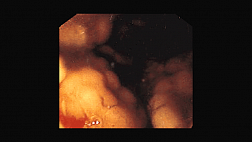

Совместно с профессором, д.м.н. НМИЦ Онкологии им. Н.Н. Блохина Ольгой Александровной Малиховой мы подготовили образовательный онлайн-семинар по актуальной тематике «Комплексная эндоскопическая диагностика нейроэндокринных опухолей и неходжкинских лимфом желудка». В режиме реального времени вы сможете увидеть прямую трансляцию из операционной по диагностике пациентов с MALT- лимфомой желудка и другими злокачественными опухолями желудка, а также задать и обсудить все интересующие вопросы.